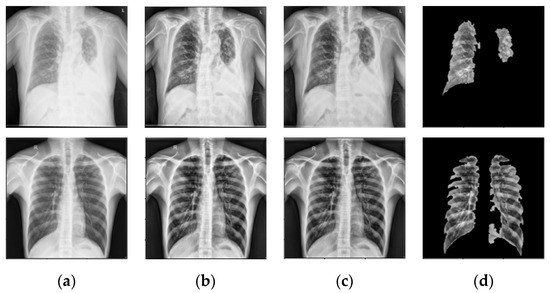

6.2. Prior TB Segmentation